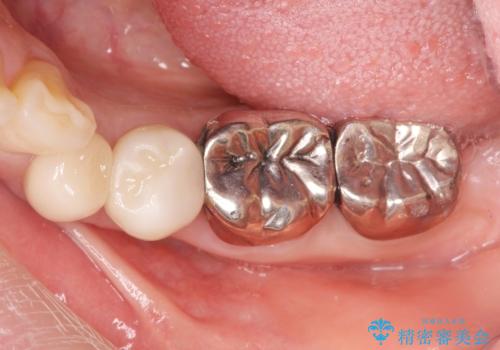

銀歯の除去 長期的な未来を見据えた虫歯治療

- 「長年使ってきた銀歯からなんとなく臭いがするので治したい、今後しっかり噛めるような歯の治療を受けたい。」

と希望され来院されました。

銀歯を除去したのち、虫歯を丁寧に除去し、歯を残せるのかどうかをしっかりと評価し、長期的な予後を見据えた虫歯治療を行っていきます。

銀歯の下で虫歯が再発していた歯は、無理に残しても割れてしまう可能性が非常に高いと考えたため、相談の上抜去を行いインプラント治療を行っていくこととしました。